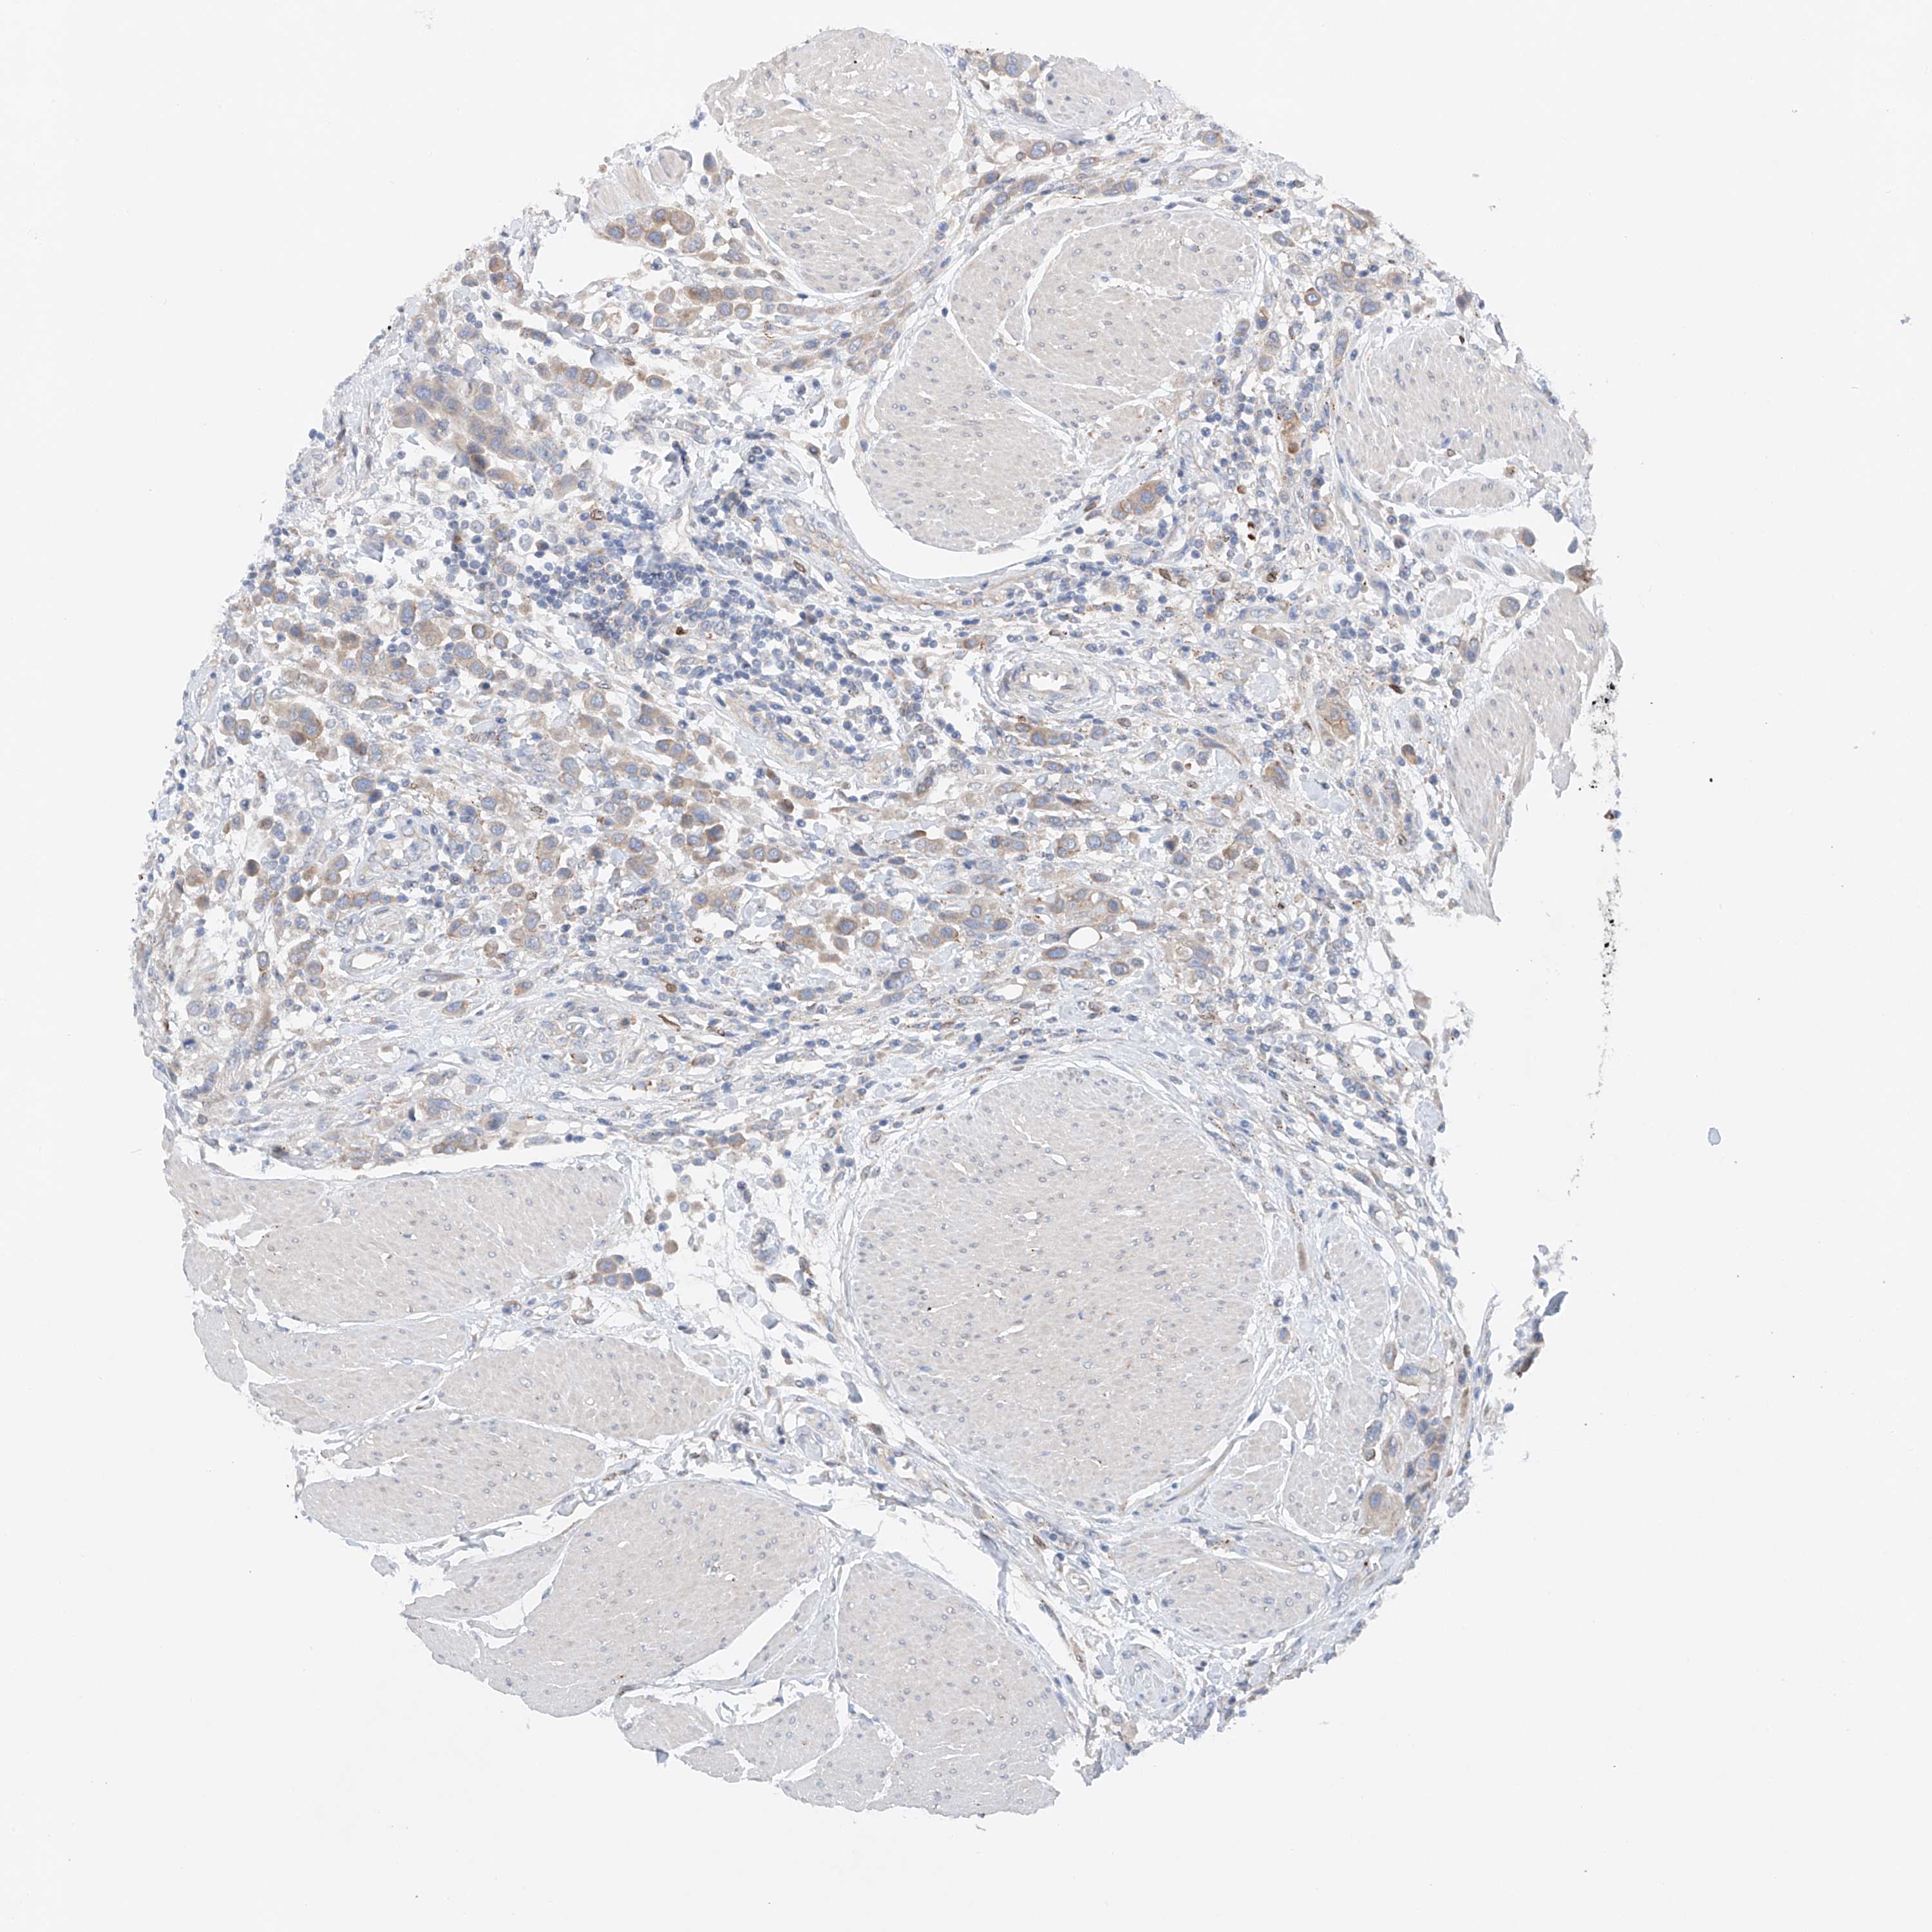

UROTHELIAL CANCER - Protein expressioni

A mouse-over function shows sample information and annotation data. Click on an image to view it in a full screen mode. Samples can be filtered based on level of antibody staining by selecting one or several of the following categories: high, medium, low and not detected. The assay and annotation is described here.

Note that samples used for immunohistochemistry by the Human Protein Atlas do not correspond to samples in the TCGA dataset.

Antibody stainingi

Antibody staining in the annotated cell types in the current human tissue is reported as not detected, low, medium, or high, based on conventional immunohistochemistry profiling in selected tissues. This score is based on the combination of the staining intensity and fraction of stained cells.

Each image is clickable and will lead to virtual microscopy that enables deeper exploration of all samples and also displays staining intensity scores, fraction scores and subcellular localization as well as patient and tissue information for each sample.

Antibody HPA029137

Antibody HPA029138

Antibody HPA029139

Staining

High

Medium

Low

Not detected

Intensity

Strong

Moderate

Weak

Negative

Quantity

>75%

75%-25%

<25%

None

Location

Nuclear

Cytoplasmic/membranous

Cytoplasmic/membranous,nuclear

Urothelial carcinoma, Low grade

Urothelial carcinoma, High grade